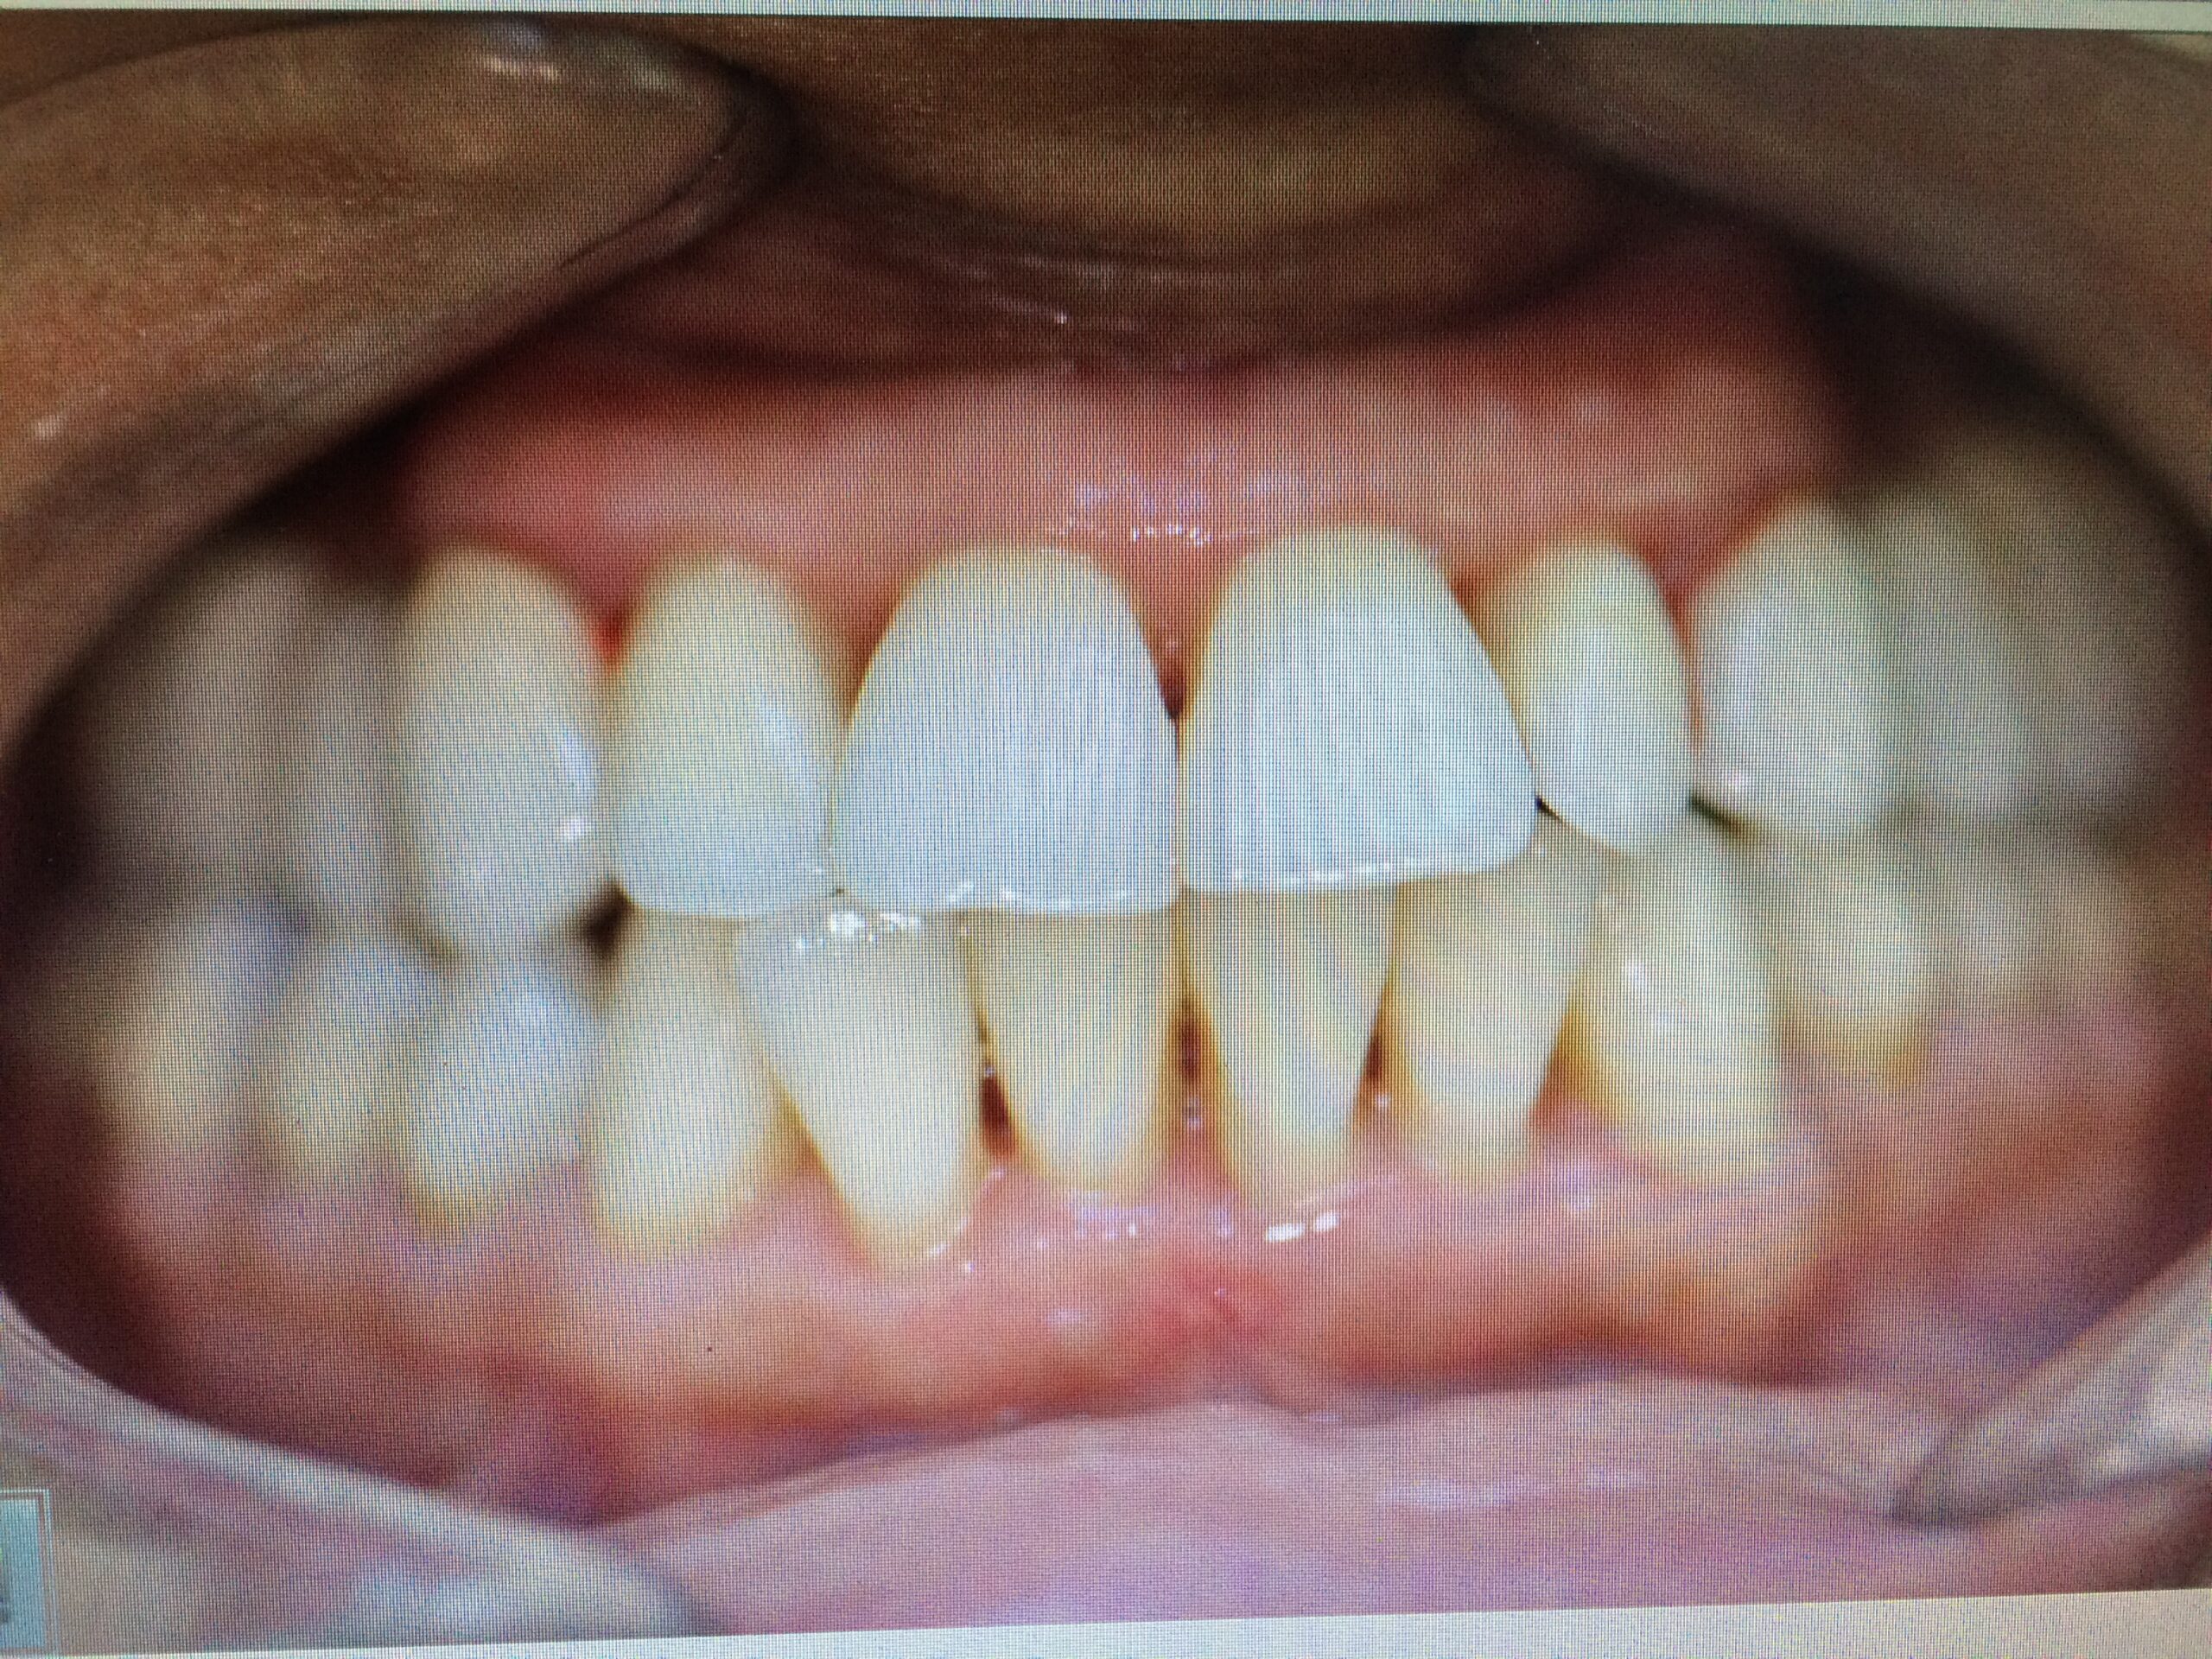

→ Les résultats sont esthétiques et permettent de redonner un sourire naturel.

→ Le sourire, la parole, la confiance sont améliorés. Un visage rajeuni, une aisance retrouvée.

→ Vous pourrez manger, parler, rire, sourire ou partir, vous vous sentirez mieux dans votre peau et dans vos relations sociales.

Les implants dentaires sont une solution durable et esthétique pour remplacer une ou plusieurs dents manquantes.

Grâce à une racine artificielle en titane insérée dans l’os de la mâchoire, l’implant offre une base solide pour fixer une couronne ou une prothèse. Cette technique permet de retrouver un sourire naturel, de préserver les os et d’éviter les déplacements des dents voisines.